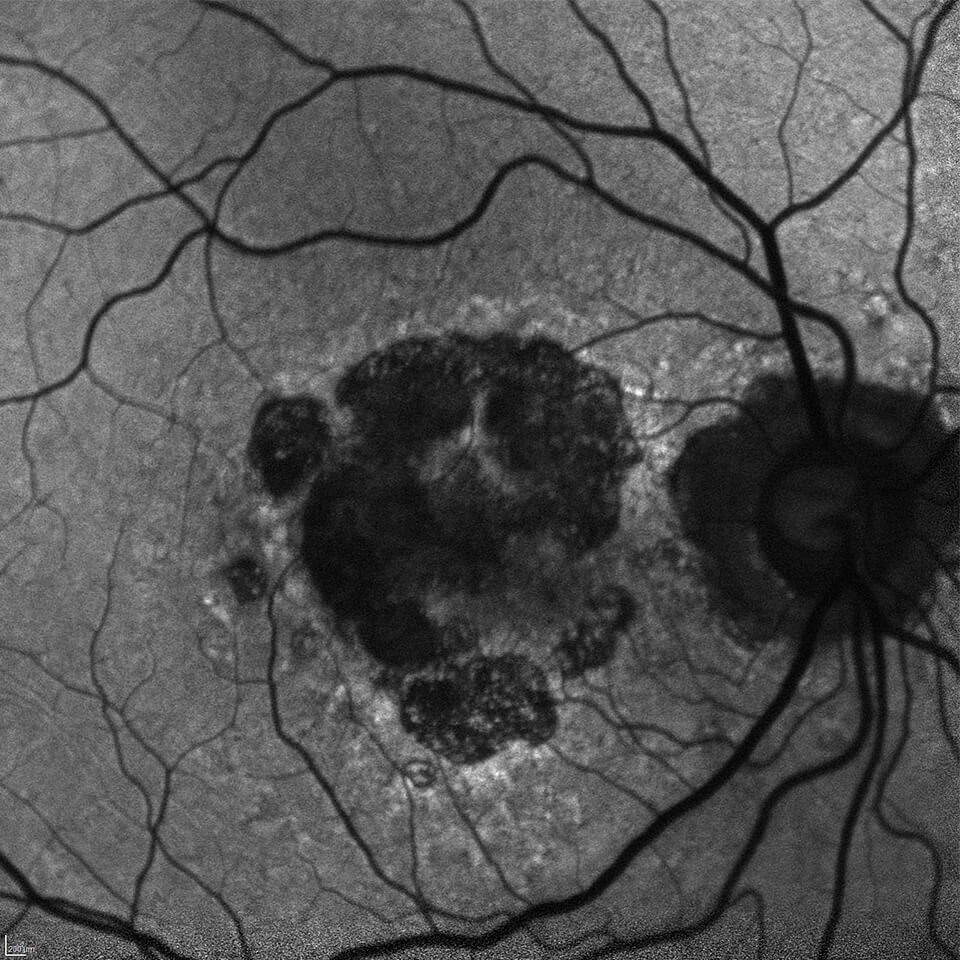

Dedicated to providing state-of-the-art treatment of eye diseases that cause vision loss by damaging the macula area of the retina.

The Clinical Research Center is dedicated to advanced clinical research in the effort to find new and more effective treatments for Age-Related Macular Degeneration (AMD) and related diseases. We offer eligible patients who suffer from these diseases the opportunity to participate in a variety of clinical research trials that may offer access to advanced new treatments not yet available to the general public. A service of Retina Consultants of Minnesota (RCM), the Clinical Research Center is supported by fifteen Retina Specialists, a dedicated full-time clinical research staff, and the state-of-the-art retina treatment facilities of RCM.

The Clinical Research Center is dedicated in fighting blindness through cutting-edge clinical research. We are one of the leading global centers committed to studying the vitreoretinal disorders.